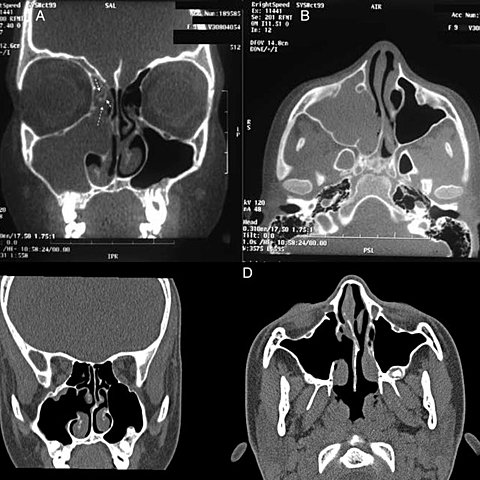

• Tomografía

Tomografía

Después de las investigaciones e innovaciones de Hounsfield en el Reino Unido, la década de los setenta fue testigo del nacimiento de la tomografía, que posiblemente fue un descubrimiento aún más importante que el de los rayos X.